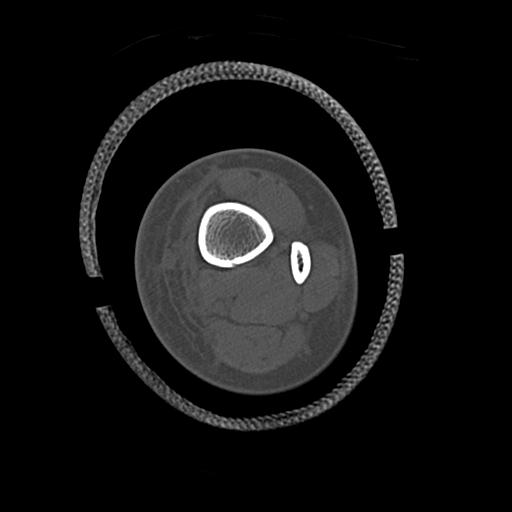

49554 3/13 膝 4R 3/16 4R 1/18 2R 78歳男性 膝蓋骨骨折